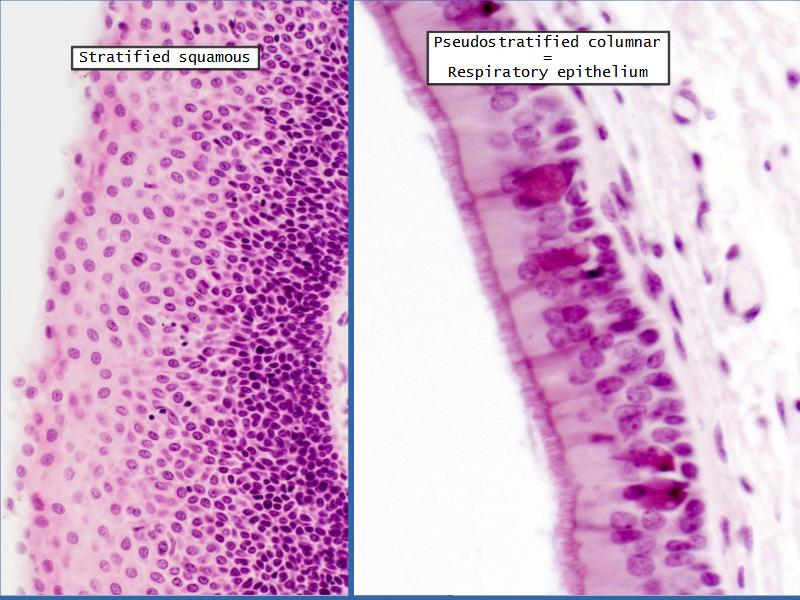

- Slide 111: Epiglottis

Epiglottis

Respiratory epithelium

- Pseudostratified

- Ciliated

- Columnar

- Epithelium with

- 4 Cells

- Ciliated columnar cells

- Non-ciliated columnar cells

- Goblet cells

- Basal cells